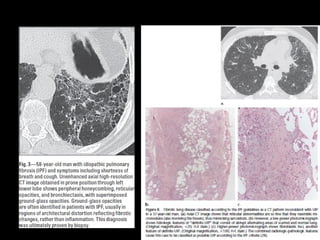

Fibrosis pulmonar idiopática

• Patrón histológico y TC: UIP

UIP histología

• Combinación heterogénea de inflamación intersticial,

fibrosis y panalización con áreas normales

• *biopsia puede desestimarse

UIP TC

• Fibrosis con áreas normales.

• Disminución de volumen pulmonar

• Opacidades reticulares

• Vidrio esmerilado

• Predominio en regiones basales y subpleurales

• Distorsión arquitectónica con bronquiectasias por tracción

secundaria a fibrosis.

• Panal de abejas (2-20mm)

• Linfoadenopatías mediastínicas pequeñas.